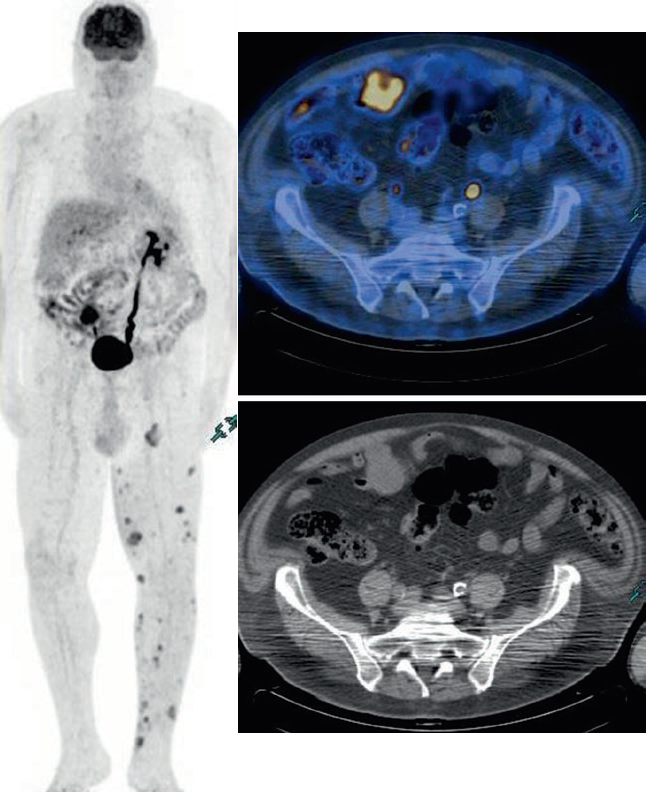

Ristadiazione di un melanoma vulvare avanzato.

La scansione PET/CT a corpo intero è fortemente suggerita negli stadi avanzati. In questo caso si hanno diverse aree di aumento dell’assorbimento a livello locale, nelle ossa, nei polmoni e nel fegato.

Sospetta ripresa addominale in paziente già operato per melanoma. Si osservano diverse aree ipermetaboliche nei linfonodi addominali e pelvici e nel torace sinistro (piccolo nodulo sottocutaneo).

La localizzazione dei siti di recidiva del melanoma può essere difficile e le immagini TC sono quasi necessarie per identificare correttamente le lesioni.